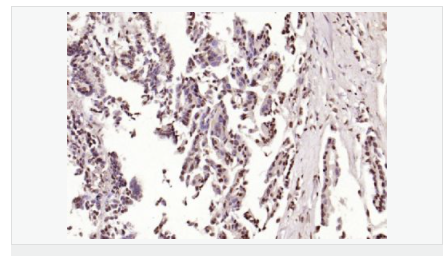

交叉反應(yīng):Human,Mouse,Rat(predicted:Dog,Pig,Rabbit,GuineaPig) 推薦應(yīng)用:IHC-P,IHC-F,ICC,IF,Flow-Cyt,ELISA

| 產(chǎn)品應(yīng)用 | ELISA=1:5000-10000 IHC-P=1:100-500 IHC-F=1:100-500 Flow-Cyt=1μg/Test ICC=1:100 IF=1:100-500 (石蠟切片需做抗原修復(fù)) not yet tested in other applications. optimal dilutions/concentrations should be determined by the end user.  |